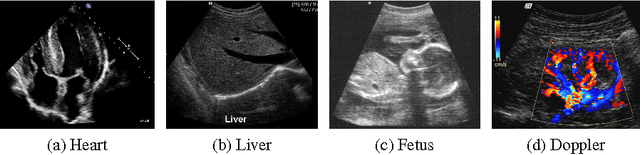

Abstract:Ultrasound is one of the most frequently used imaging modality in medicine. The high spatial resolution, its interactive nature and non-invasiveness makes it the first choice in many examinations. Image interpretation is one of ultrasound's main challenges. Much training is required to obtain a confident skill level in ultrasound-based diagnostics. State-of-the-art graphics techniques is needed to provide meaningful visualizations of ultrasound in real-time. In this paper we present the process-pipeline for ultrasound visualization, including an overview of the tasks performed in the specific steps. To provide an insight into the trends of ultrasound visualization research, we have selected a set of significant publications and divided them into a technique-based taxonomy covering the topics pre-processing, segmentation, registration, rendering and augmented reality. For the different technique types we discuss the difference between ultrasound-based techniques and techniques for other modalities.